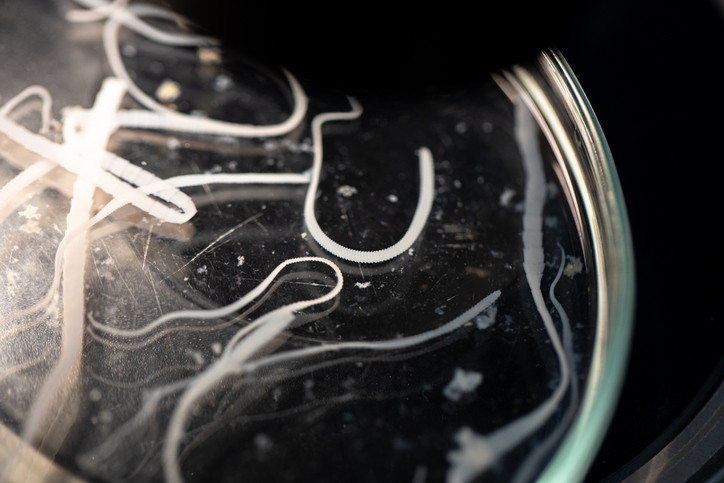

Uzmanlar paraziti “Ophidascaris robertsi” adlı bir yuvarlak solucanın üçüncü evre larvası olarak tanımladı. Bu parazit normalde Avustralya’ya özgü halı pitonlarının bağırsaklarında yaşıyor ve bugüne kadar insanlarda enfeksiyon yaptığına dair bir kayıt bulunmuyordu.

Araştırmacılar kadının göl kenarındaki evinin çevresinde pitonların yaygın olduğunu, sık sık doğadan yabani ot toplayarak yemek yaptığı için parazitin yumurtalarıyla kirlenmiş bitkilere temas etmiş veya onları tüketmiş olabileceğini düşünüyor. Yumurtaların vücuda girdikten sonra açıldığı ve larvaların akciğer, karaciğer ve en sonunda beyne kadar göç ettiği değerlendiriliyor.